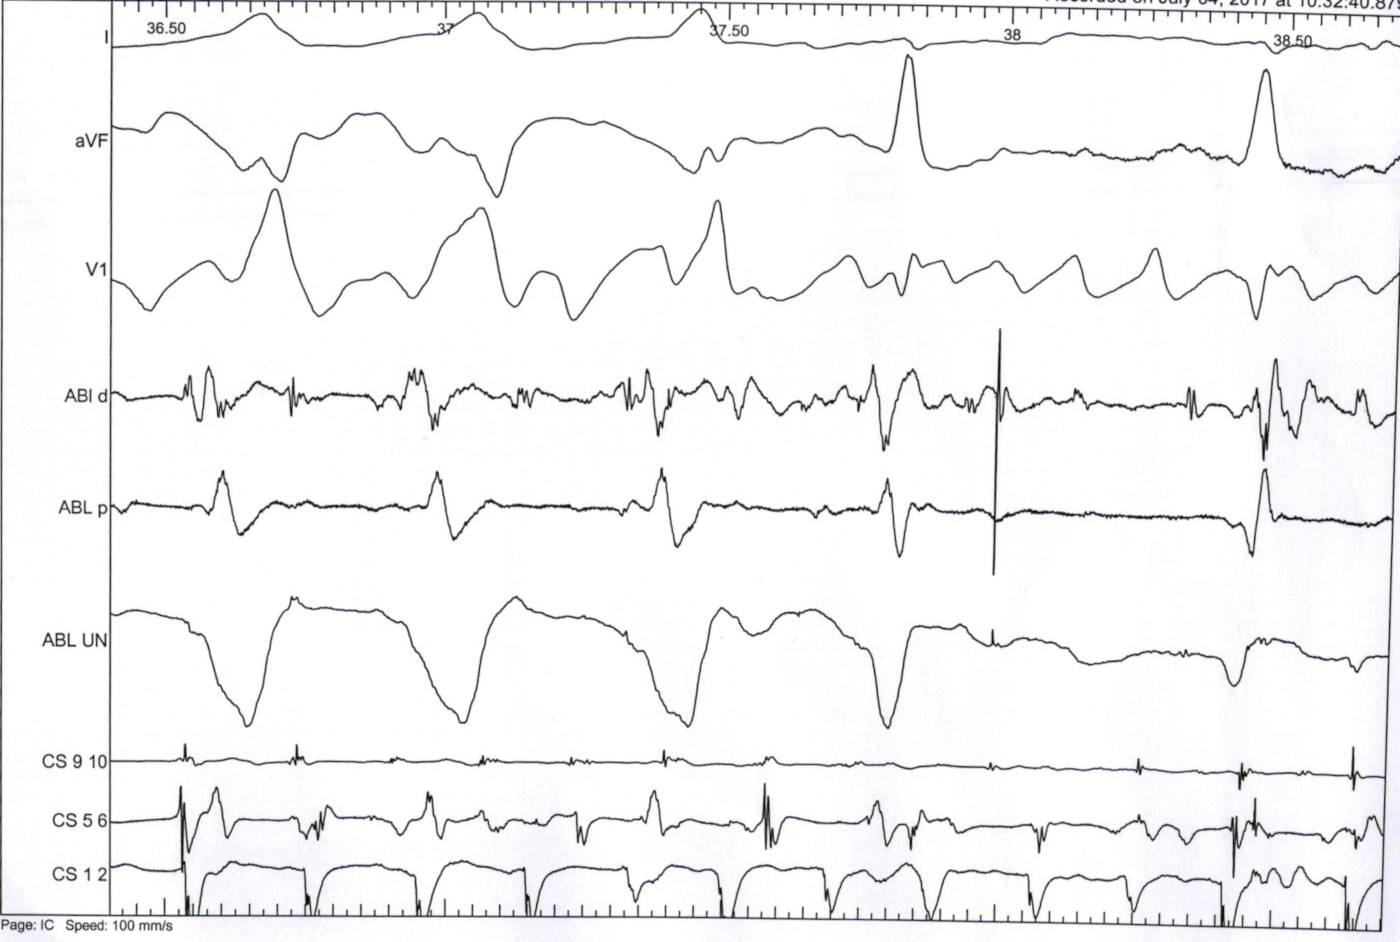

VA block during ablation

06_tachy.jpg

08_va_block_abl.jpg

09_a_pace_abl.jpg